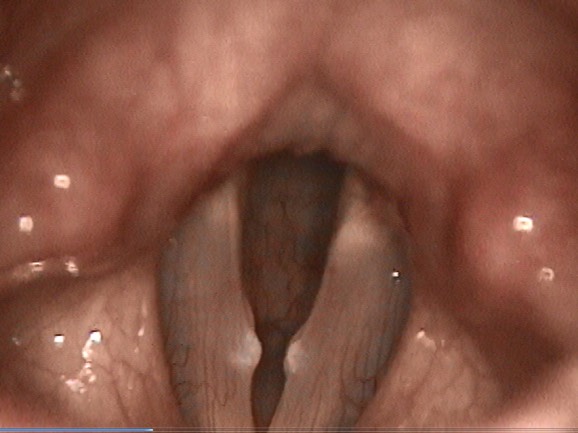

2240. Данная ларингоскопическая картина позволяет поставить диагноз